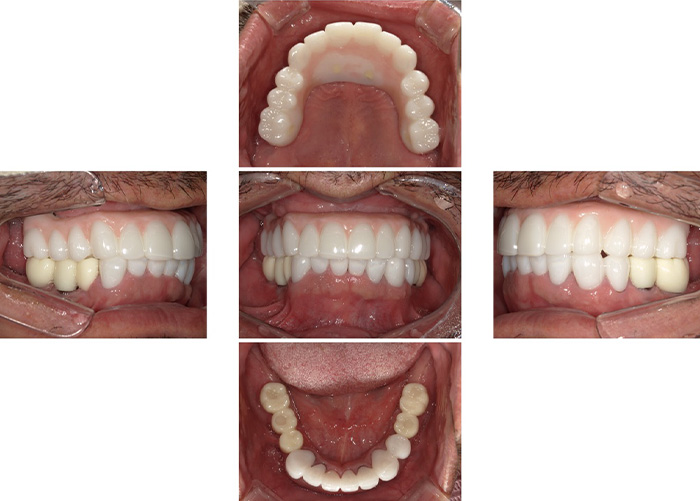

Case.04

![]() |

|---|

| 主訴 | 上も下もぐらぐらしたり腫れたりして噛めない |

|---|---|

| 治療期間 | 1年 |

| 治療費 | 300,000円(税込330,000円)上顎All On 4 |

| 治療内容 | 4本のインプラントを入れて、12本の歯を支えます。 抜歯当日にインプラントを入れて、仮歯を装着します。 |

| 治療のリスク | インプラントは歯周病になる可能性があります。 一定の割合で生着しないで再埋入が必要になる場合があります。 |